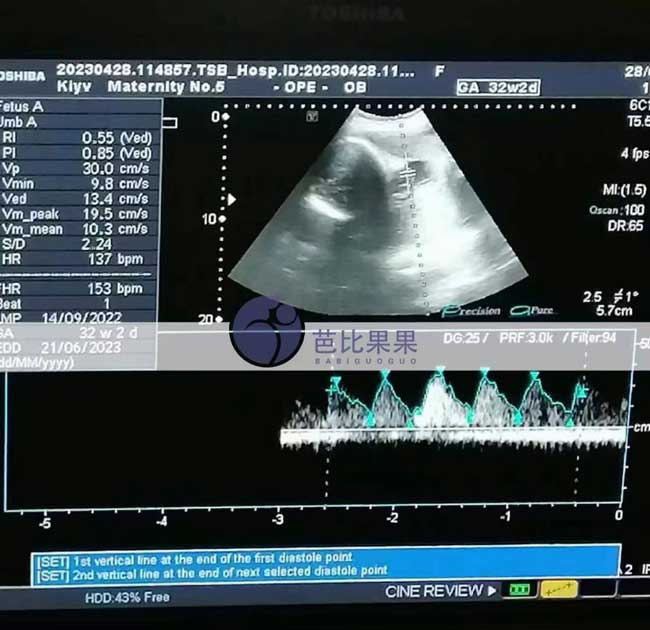

Z女士的乌克兰试管妈妈准时来妇产医院做了32周B超孕检,胎儿发育得不错,很快就要破壳啦